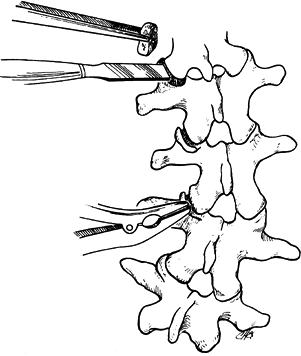

In the thoracic spine, use a Capner gouge

to remove a generous portion of the inferior facets on both the concave

and convex sides of the curve. -

With a curet, remove the visible

cartilage. Then use the gouge to decorticate the superior portion of

the junction of the transverse process and the facet. Pack a generous

piece of cancellous bone into the facet with the Moe bone impactor (Fig. 156.7).

Figure 156.7. The techniques used for excising the thoracic joint (A) and packing with cancellous bone (B). -

In the lumbar spine, the facet joints can

be excised using a straight ¼-inch Lambotte osteotome or a Lexcel

rongeur. It is important to see the joint and remove the articular

cartilage completely (Fig. 156.8). Then pack a piece of cancellous bone into place with the Moe impactor.

Figure 156.8. The technique used for excising lumbar facets and packing with cancellous bone plugs. -